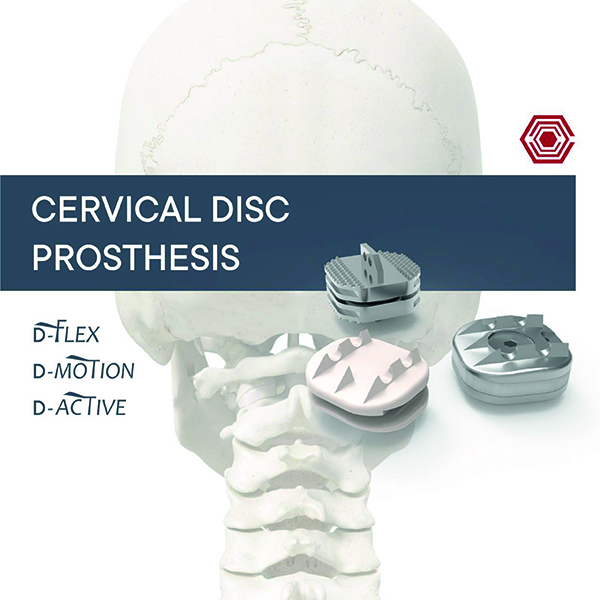

Cervical Disc Prosthesis

Akif Kaya Aybek

Norm Akademi

- Surgical Technique

- Kinematics

- Materials

- Sizes

- Instrument Container

- Instrument Types